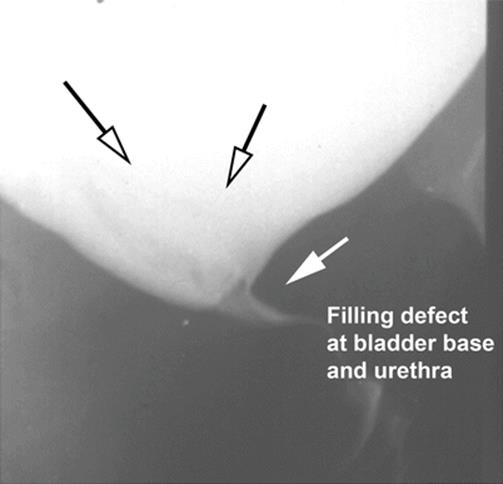

8.3 Ectopic Ureterocele Presenting as a Vaginal Cyst

The patient, 23 years old, presented with difficulty in emptying the bladder, recurrent urinary infection, and distal urethral pain. Figures 8.11, 8.12, 8.13, and 8.14 illustrate the finding of an ectopic ureterocele. The patient had a side-to-side anastomosis of the ureters, with ligature of the affected ureter. The urethral cyst and her voiding dysfunction were corrected and she remained asymptomatic.

Fig. 8.13

A voiding cystogram showing a filling defect of the bladder base extending toward the urethra. The arrows delineated the cystic defect